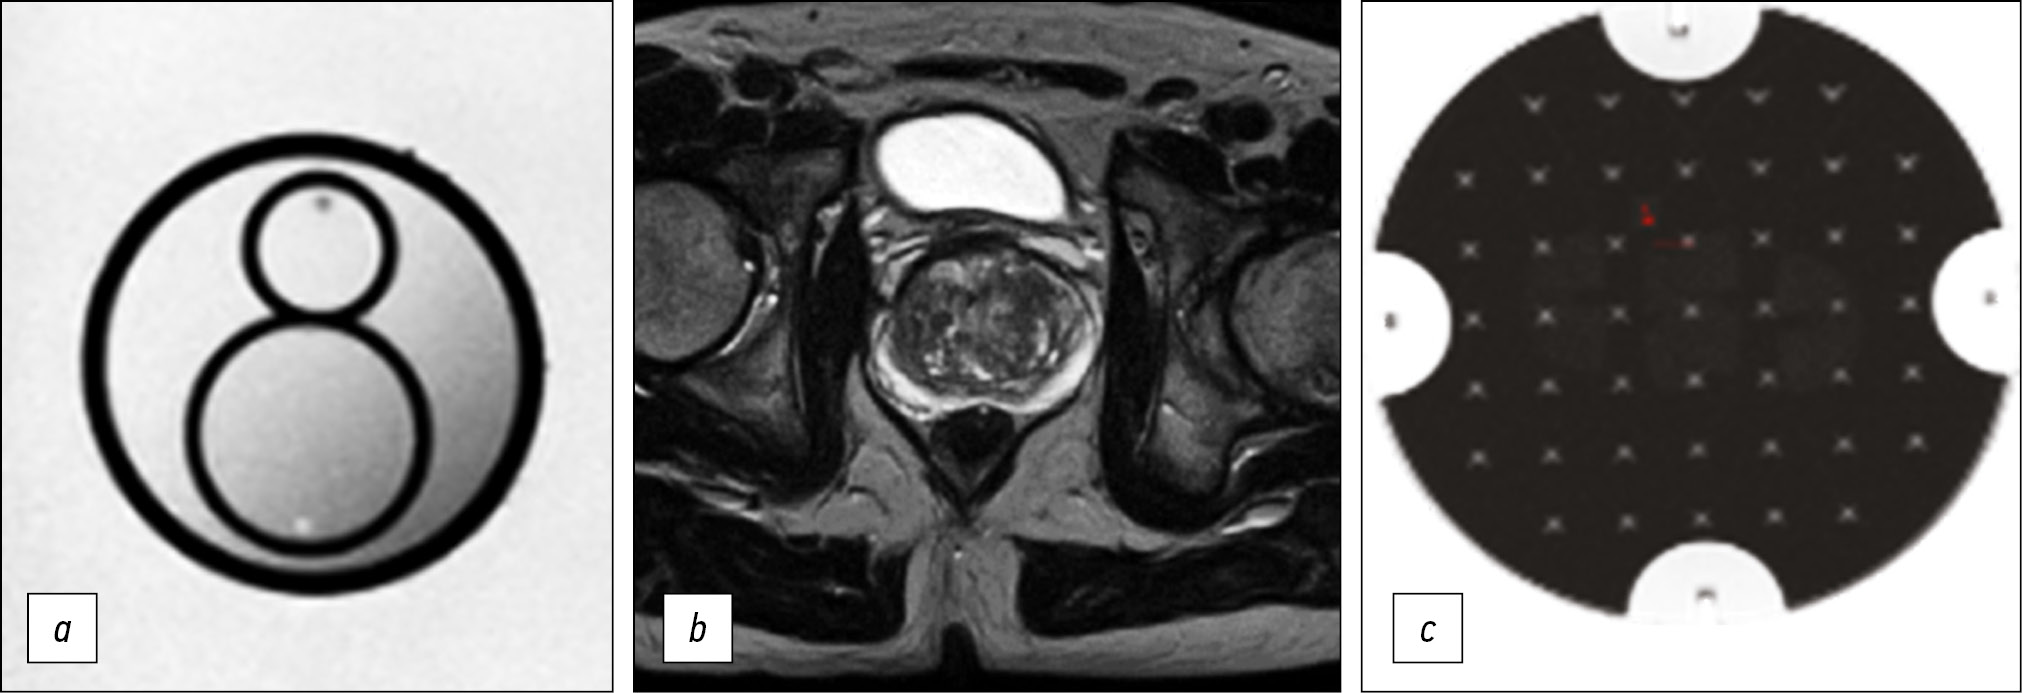

Материалы и методы. Предварительный анализ полученных магнитно-резонансных изображений предстательной железы в медицинских организациях Департамента здравоохранения города Москвы показал отсутствие единого подхода к выполнению данного исследования. Методом итерационной корректировки параметров сканирования нами был настроен протокол, обеспечивающий приемлемое качество визуализации при максимально возможном соответствии требованиям PI-RADS. Для количественной оценки качества получаемых изображений применялся фантом для контроля магнитно-резонансной томографии, рекомендованный Американским обществом рентгенологов.

Результаты. Разработан оптимизированный бипараметрический протокол для томографа Excelart Vantage 1,5 Т, включающий Т2-взвешенные изображения в трёх плоскостях и диффузионно-взвешенные изображения общей длительностью менее 11 мин. При этом обеспечен высокий уровень детализации предстательной железы, а параметры качества изображения (неоднородность яркости, нелинейность, разрешающая способность и толщина выделяемого среза) соответствовали допустимым производителем диапазонам.